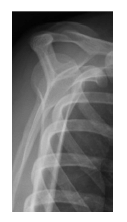

Analise a imagem ao lado:

Qual incidência radiográfica é mostrada nesta imagem?

perfil da escápula

incidência de abertura

rotação externa do ombro

axial inferossuperior

AP da escápula